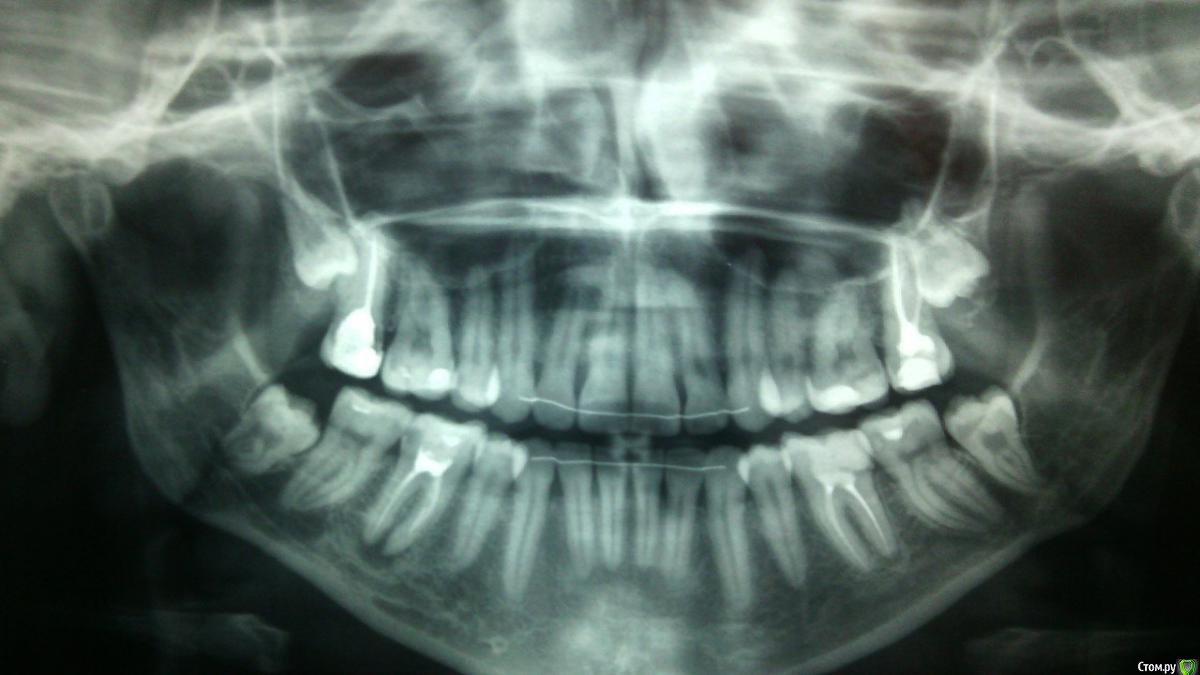

Евгения_87 Опубликовано 26 февраля, 2015 Поделиться Опубликовано 26 февраля, 2015 Добрый день!При планировании беременности решила сделать ОПТГ. На снимке обнаружилась киста 46 зуба на оба корня...Зуб абсолютно не беспокоит, не болит, на температуру не реагирует, не шатается, был депульпирован лет 10-12 назад... Только на внешний вид эмаль потемнела до серого цвета.Обзвонила все клиники города, оказалось что эндодонтистов с соответствующим оборудованием у нас нет!Сходила на консультации к нескольким врачам (от терапевта до хирурга) никто не берется лечить, советуют удалять зуб с последующей имплантацией.Я в расстройстве...неужели зуб настолько безнадежен? Хотелось бы вылечить и сохранить!Прилагаю снимок и надеюсь на помощь и совет, стоит ли бороться за зуб или удаление неизбежно? Ссылка на комментарий

Чертков Александр Опубликовано 26 февраля, 2015 Поделиться Опубликовано 26 февраля, 2015 Добрый день. Зуб подлежит лечению и сохранению. Последующее восстановление искусственной коронкой (обязательно!). Обратите внимание на зуб противоположной стороны (3.6) - схожая проблема (чуть меньших размеров). Обязательно сделать прицельный снимки 1.7, 2.7. Ну и с 8ми я бы рекомендовал расстаться. 2 Ссылка на комментарий

Евгения_87 Опубликовано 12 марта, 2015 Автор Поделиться Опубликовано 12 марта, 2015 Спасибо за ответы!Была в очередной раз у терапевта, заново сделали снимки и обнаружили обломок инструмента в одном из каналов! Вот откуда и очаг инфекции пошел! А сама киста пока еще в стадии гранулемы 6х8 мм...Врач сказала, что может попробовать лечить...но исход во многом будет зависеть от того сможет ли она извлечь или обойти осколок (что весьма трудно). Гарантии на успешный исход, конечно, же не дает... все на страх и риск пациента. И еще сказала, что стенки зуба очень истончены и впоследствии (при успешном результате) нужно будет коронку ставить!Спросила нужно ли мне вкладывать деньги вслепую или лучше подкопить на имплант, и отправила домой думать...Вот сижу в размышлениях.... Ссылка на комментарий